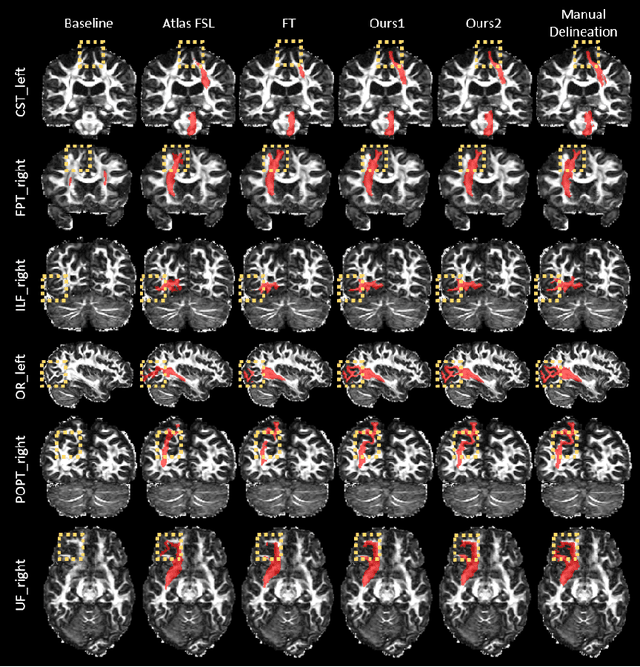

Abstract:Deep learning based methods have achieved state-of-the-art performance for automated white matter (WM) tract segmentation. In these methods, the segmentation model needs to be trained with a large number of manually annotated scans, which can be accumulated throughout time. When novel WM tracts, i.e., tracts not included in the existing annotated WM tracts, are to be segmented, additional annotations of these novel WM tracts need to be collected. Since tract annotation is time-consuming and costly, it is desirable to make only a few annotations of novel WM tracts for training the segmentation model, and previous work has addressed this problem by transferring the knowledge learned for segmenting existing WM tracts to the segmentation of novel WM tracts. However, accurate segmentation of novel WM tracts can still be challenging in the one-shot setting, where only one scan is annotated for the novel WM tracts. In this work, we explore the problem of one-shot segmentation of novel WM tracts. Since in the one-shot setting the annotated training data is extremely scarce, based on the existing knowledge transfer framework, we propose to further perform extensive data augmentation for the single annotated scan, where synthetic annotated training data is produced. We have designed several different strategies that mask out regions in the single annotated scan for data augmentation. Our method was evaluated on public and in-house datasets. The experimental results show that our method improves the accuracy of one-shot segmentation of novel WM tracts.

Abstract:Convolutional neural networks (CNNs) have achieved stateof-the-art performance for white matter (WM) tract segmentation based on diffusion magnetic resonance imaging (dMRI). These CNNs require a large number of manual delineations of the WM tracts of interest for training, which are generally labor-intensive and costly. The expensive manual delineation can be a particular disadvantage when novel WM tracts, i.e., tracts that have not been included in existing manual delineations, are to be analyzed. To accurately segment novel WM tracts, it is desirable to transfer the knowledge learned about existing WM tracts, so that even with only a few delineations of the novel WM tracts, CNNs can learn adequately for the segmentation. In this paper, we explore the transfer of such knowledge to the segmentation of novel WM tracts in the few-shot setting. Although a classic fine-tuning strategy can be used for the purpose, the information in the last task-specific layer for segmenting existing WM tracts is completely discarded. We hypothesize that the weights of this last layer can bear valuable information for segmenting the novel WM tracts and thus completely discarding the information is not optimal. In particular, we assume that the novel WM tracts can correlate with existing WM tracts and the segmentation of novel WM tracts can be predicted with the logits of existing WM tracts. In this way, better initialization of the last layer than random initialization can be achieved for fine-tuning. Further, we show that a more adaptive use of the knowledge in the last layer for segmenting existing WM tracts can be conveniently achieved by simply inserting a warmup stage before classic fine-tuning. The proposed method was evaluated on a publicly available dMRI dataset, where we demonstrate the benefit of our method for few-shot segmentation of novel WM tracts.